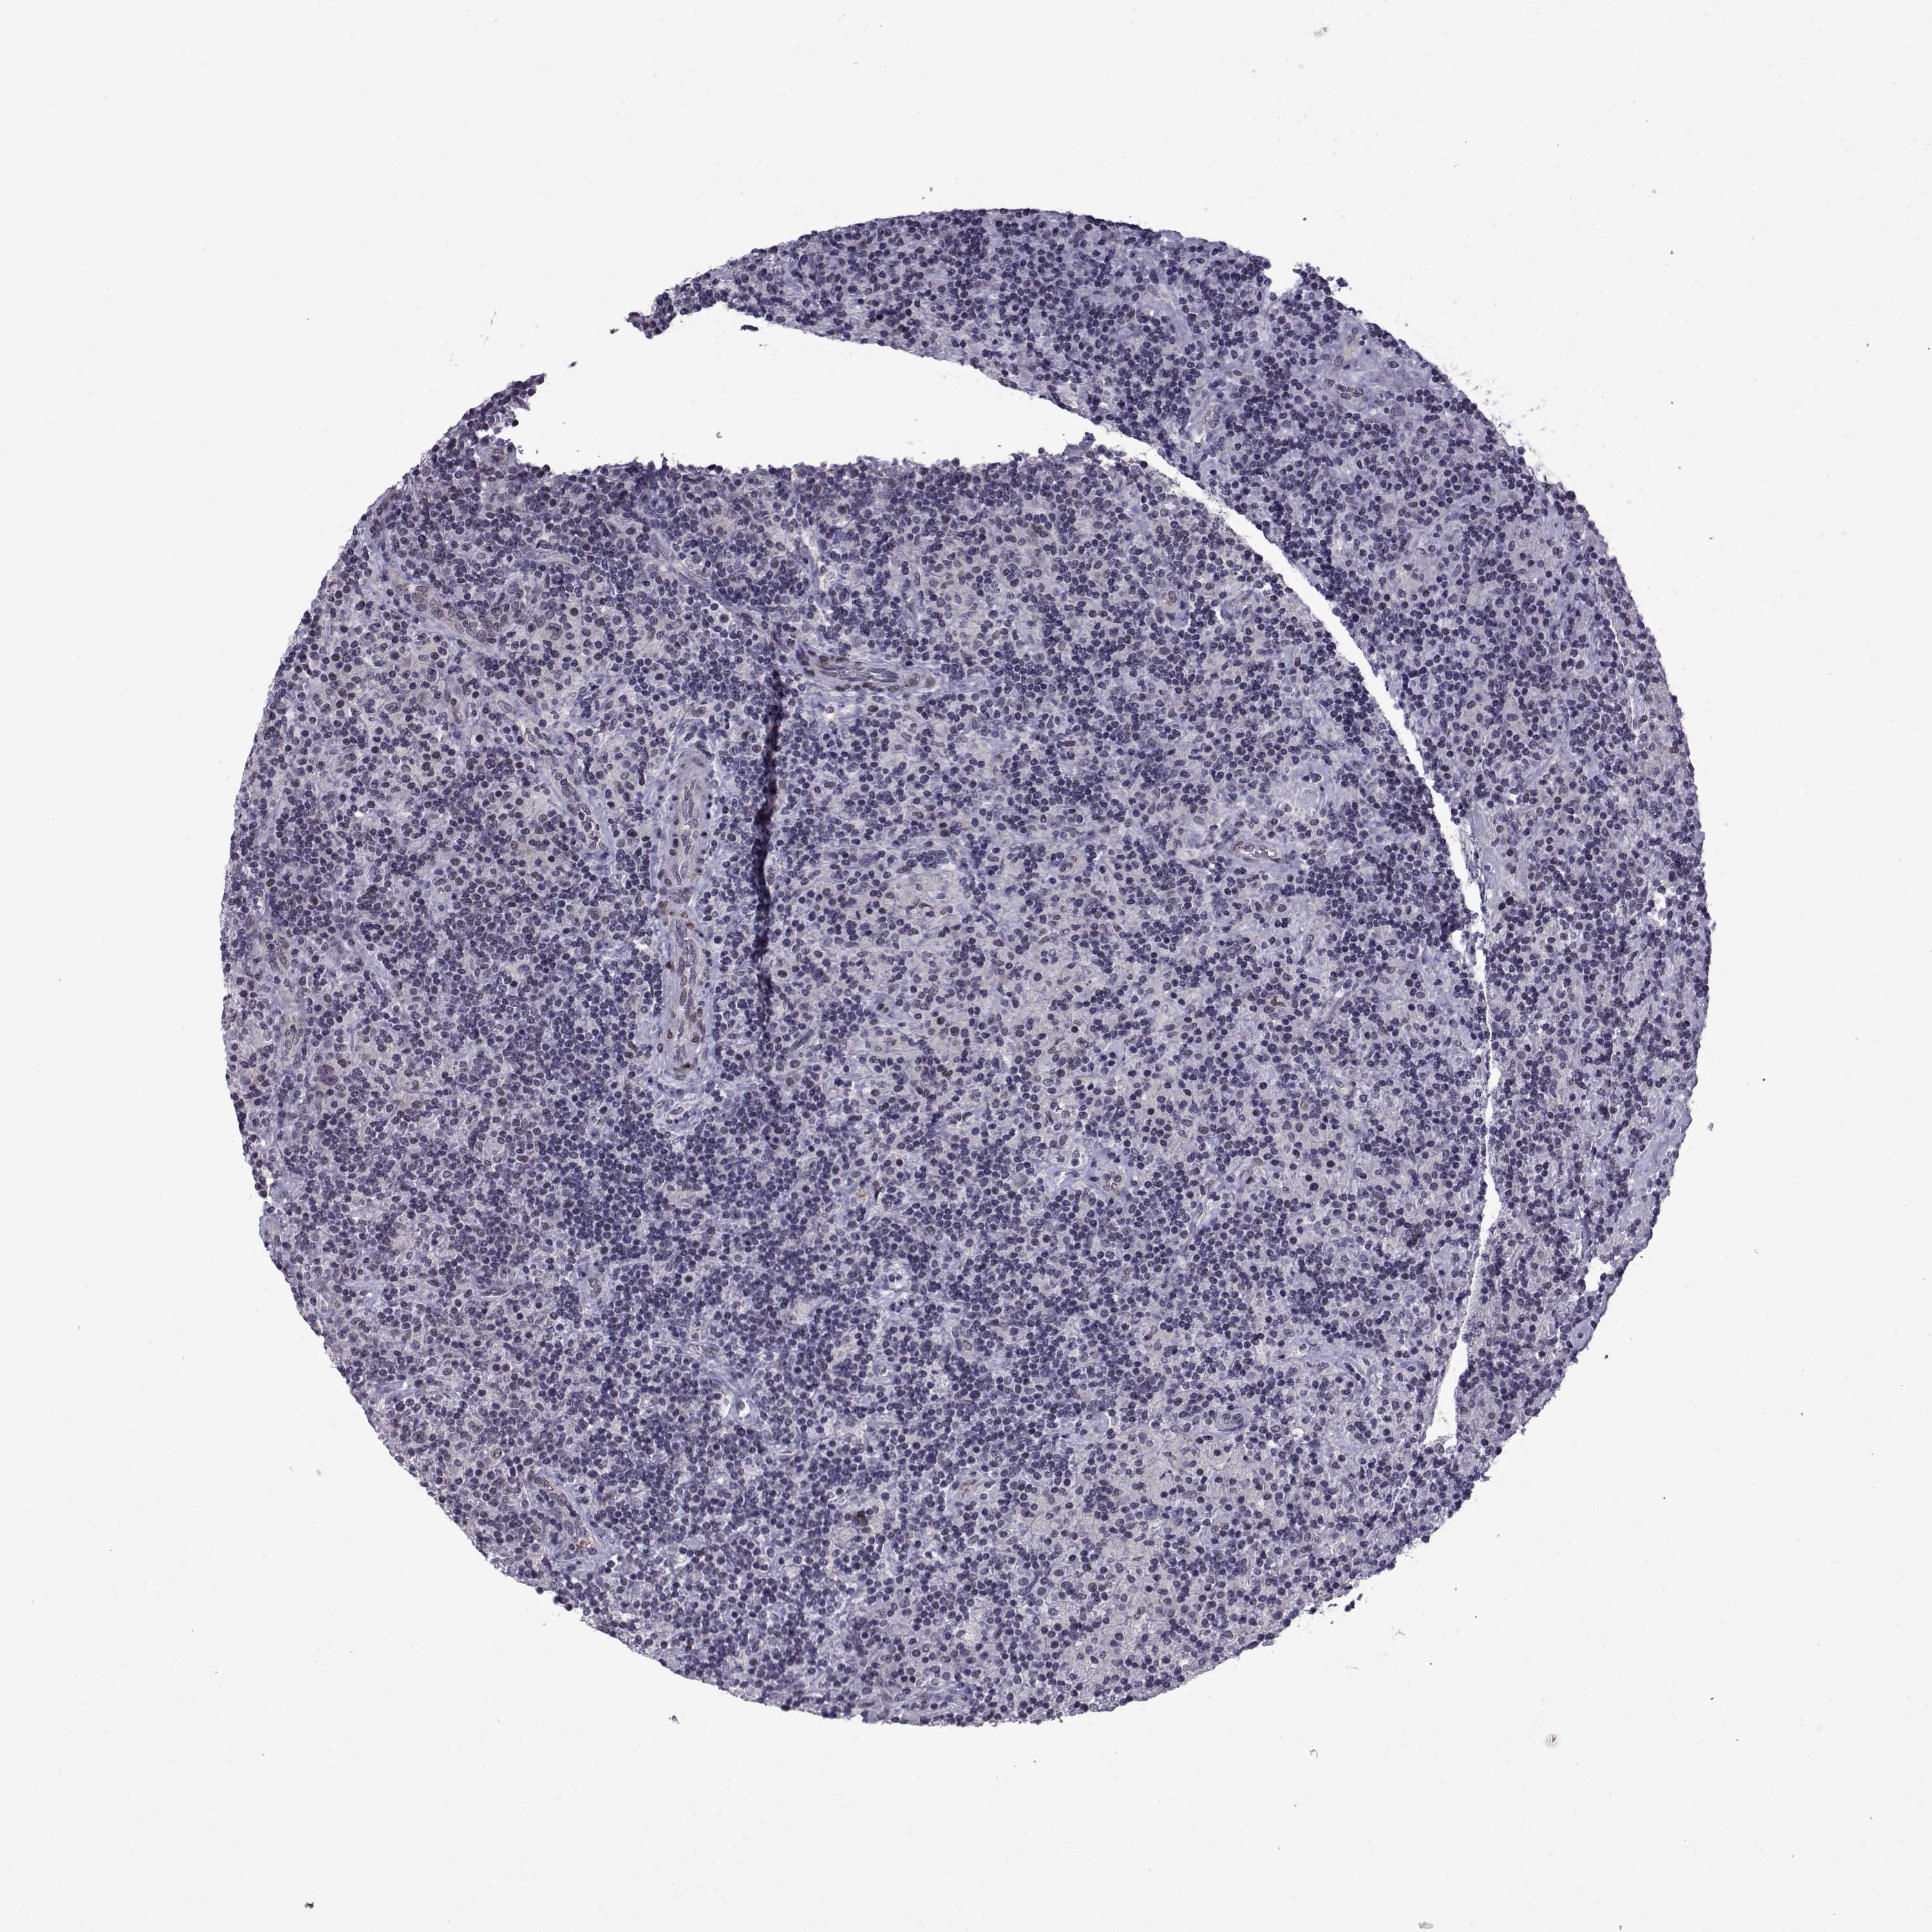

CANCER LYMPHOMA Show tissue menu

LYMPHOMA - Protein expressioni

A mouse-over function shows sample information and annotation data. Click on an image to view it in a full screen mode. Samples can be filtered based on level of antibody staining by selecting one or several of the following categories: high, medium, low and not detected. The assay and annotation is described here.

Each image is clickable and will lead to virtual microscopy that enables deeper exploration of all samples and also displays staining intensity scores, fraction scores and subcellular localization as well as patient and tissue information for each sample.

Antibody HPA066927

Staining

High

Medium

Low

Not detected

Intensity

Strong

Moderate

Weak

Negative

Quantity

>75%

75%-25%

<25%

None

Location

Nuclear

Cytoplasmic/membranous

Cytoplasmic/membranous,nuclear

Malignant lymphoma, non-Hodgkin's type, Low grade

Malignant lymphoma, non-Hodgkin's type, High grade

Hodgkin's disease, NOS